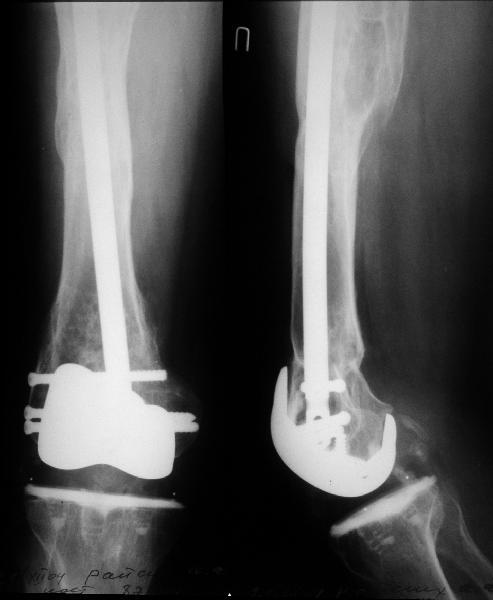

MTA> 2). There is rather limited room between the condyles in an IB2 knee for

MTA> a retrograde nail.

Go antegrade if you have an approriate implant available. Attached is a result of a similar fracture.